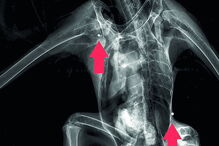

Ave ficou ferida após ser atingida com tiros de caçadeira.

A águia, que tem o estatuto de ‘Quase Ameaçada’ em Portugal, terá sido alvejada também no Alentejo, em meados de agosto. Foi encontrada em Moura e depois levada para o RIAS. No centro, o exame radiológico detetou três projéteis de caçadeira: na cabeça, ombro direito e costado esquerdo. Foram ainda descobertos restos de um quarto projétil.